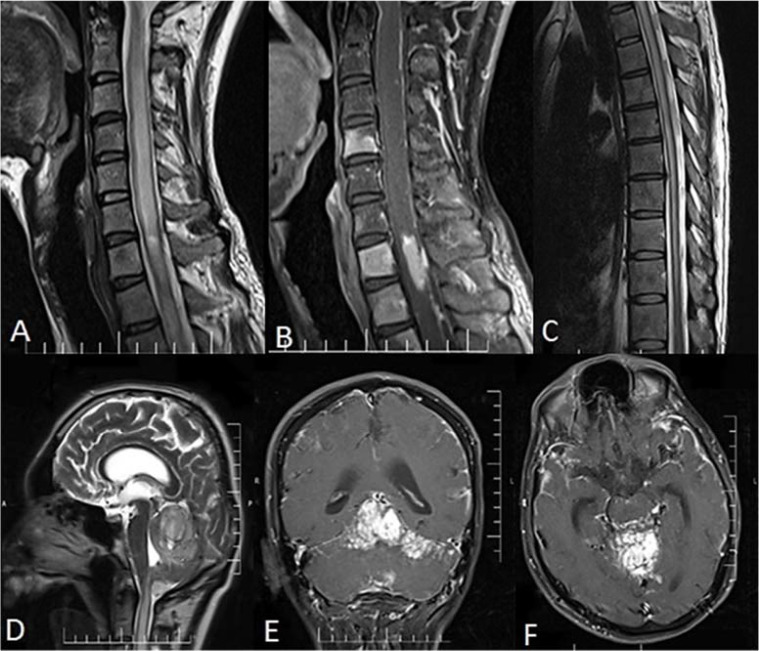

Diffuse leptomeningeal glioneuronal tumor (DLGNT) with hydrocephalus as an initial symptom mimicking tuberculous meningitis: A case report.